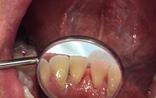

Figura 2. Vista lingual inferior dientes con sarro.

En la Figura 2 se ven los organos dentarios del 32 al 42 con sarro en la superficie lingual abarcando menos del tercio medio.